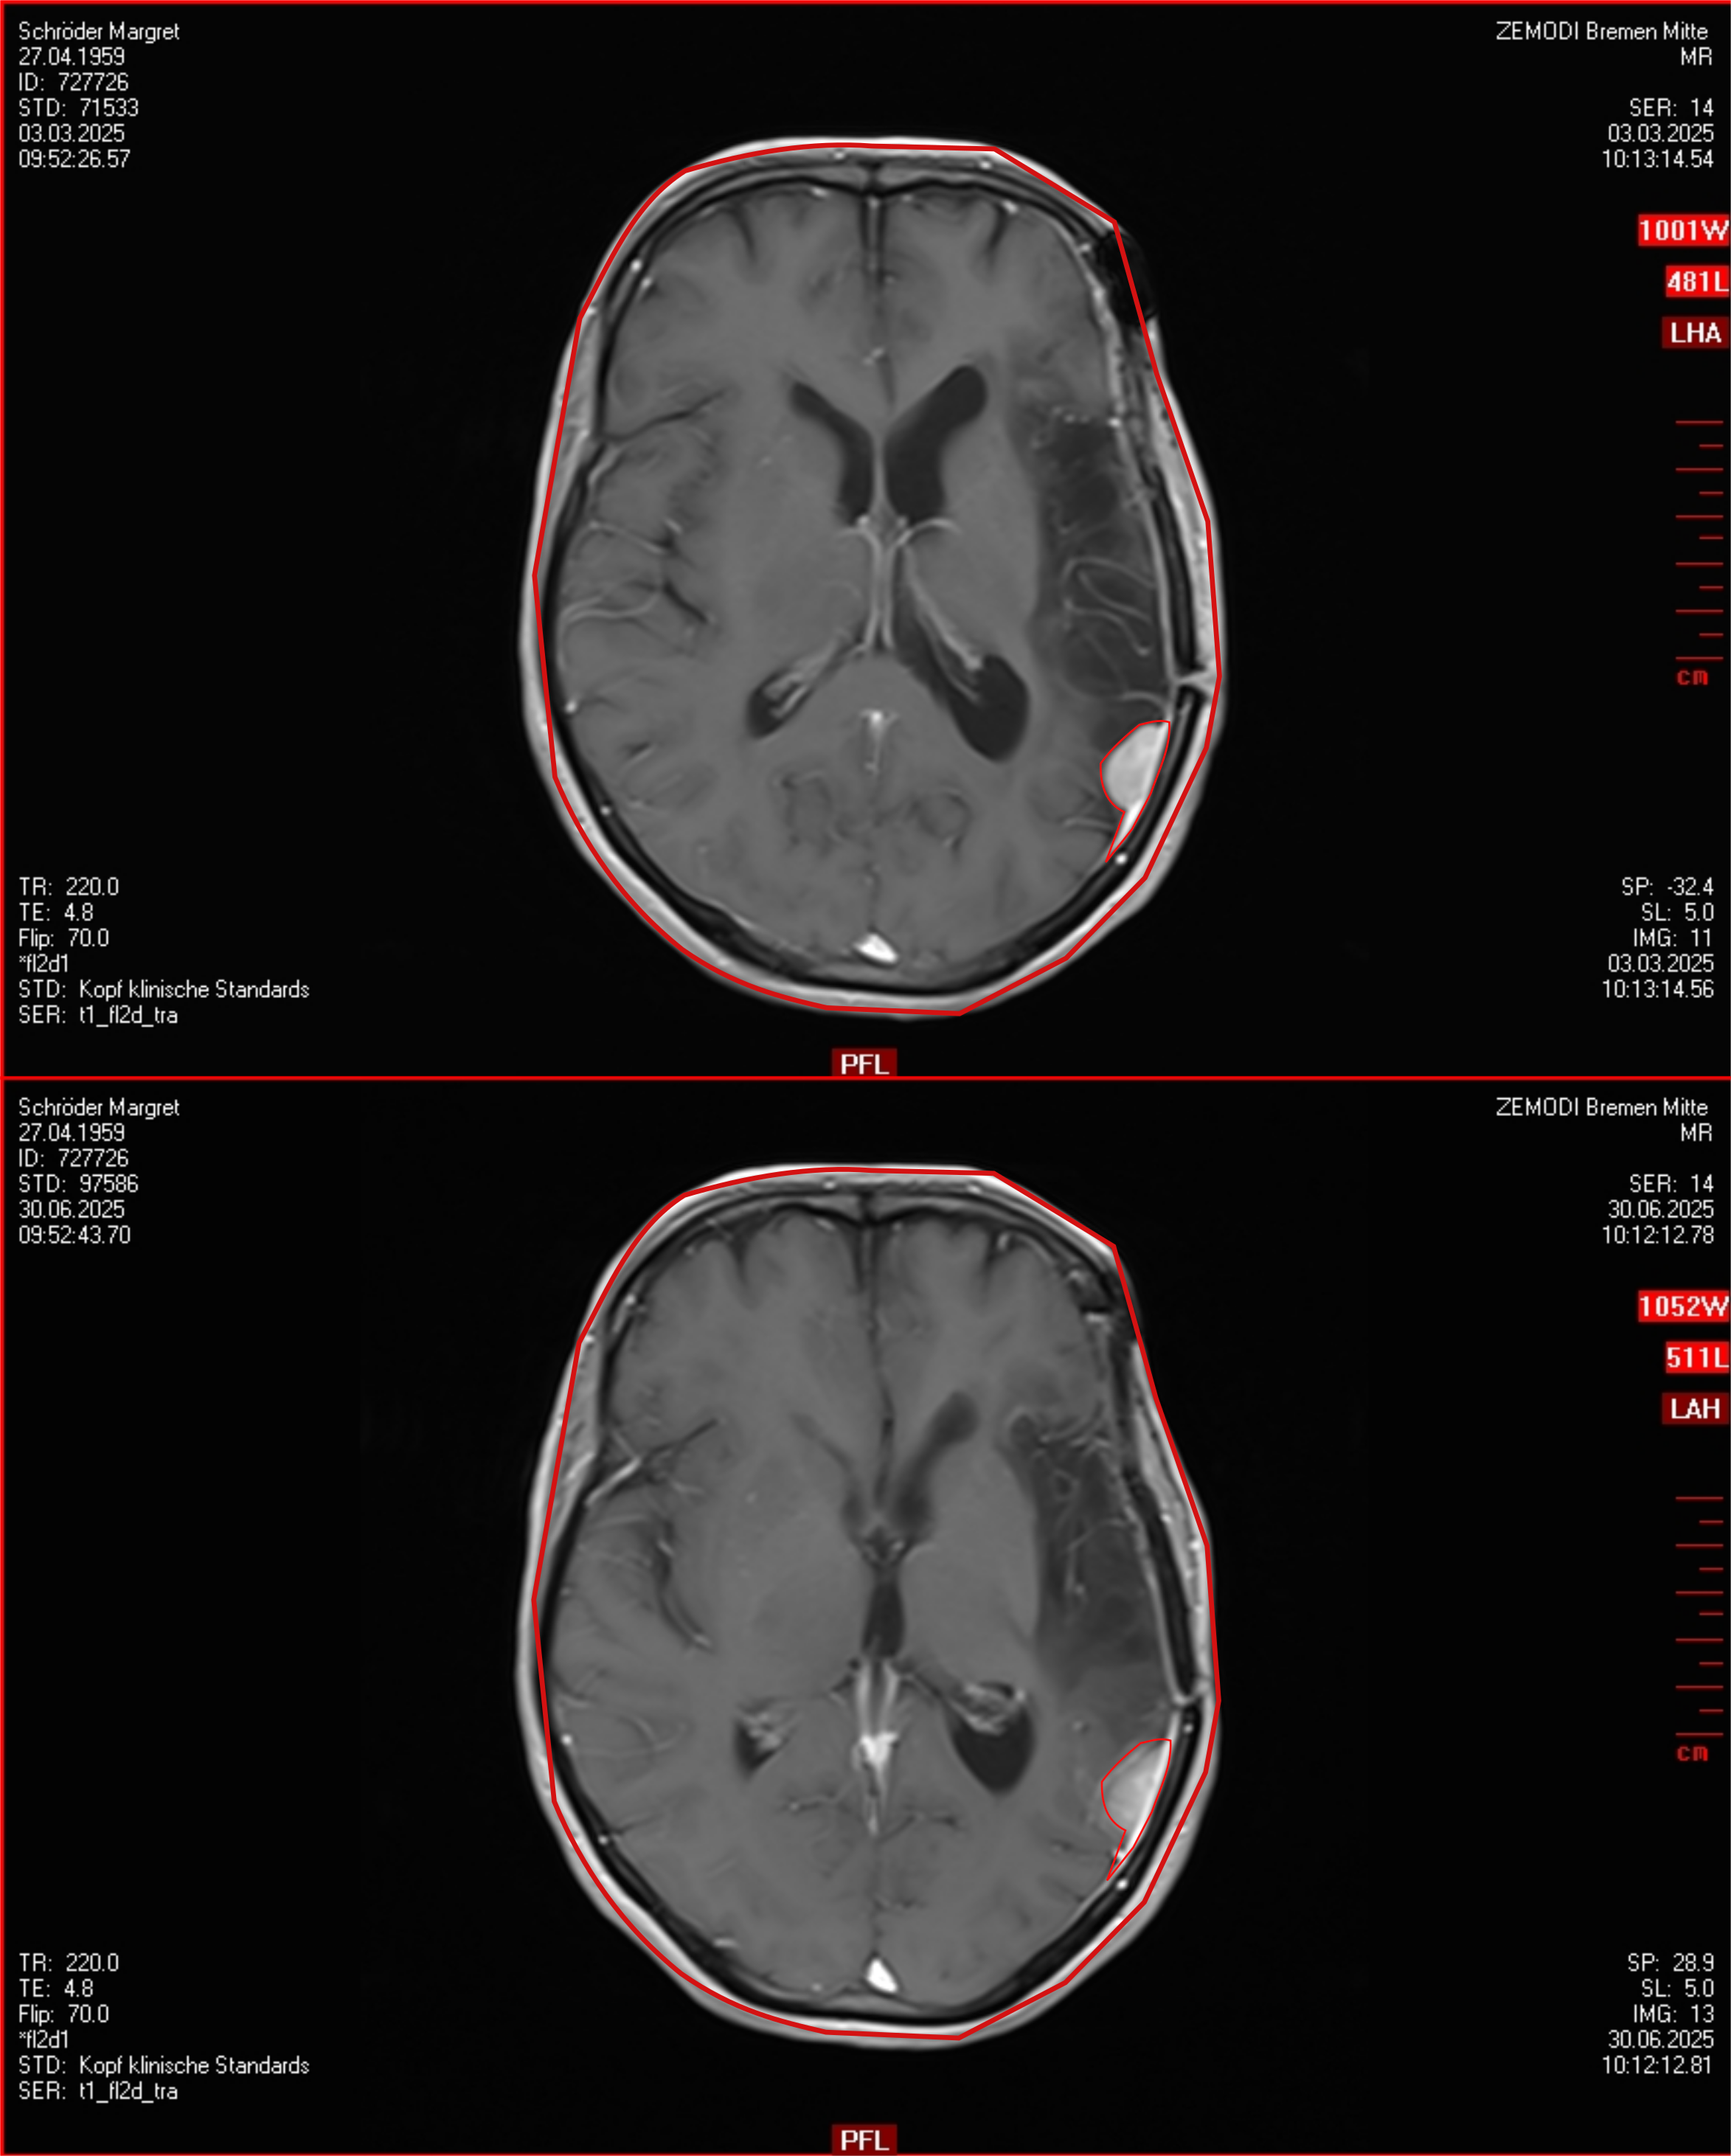

Gewachsen?! Entscheidung vertagt.

Am 30.06.25 war ich beim MRT. Es hat kein Gespräch mit dem Radiologen stattgefunden - drei MRT-Geräte und nur ein Arzt anwesend. Naja. Der Bericht war schnell bei der Hausärztin, beim Verstehen musste diesmal ChatGPT helfen. Ein Tumor ist gewachsen - einer von denen, die im Gamm-Knife bestrahlt wurden. Am 02.07.2025 war ich in der Ambulanz der Neurochirulogie des Krankenhauses. Dort die gleiche Ausage. Nun warte ich mal auf die Aussage der Tumorkonferenz. Vorsorglich habe ich die Bilder auch nach Hamburg zur Gamma-Knife Praxis geschickt.

Weil ich ja auch immer selber schaue, habe ich hier eine kleine Studie versucht. Und weil meine Geschichte so unübersichtlich ist, habe ich auch eine Tabelle mit der Historie erstellt. Nun weiss ich, dass ich noch etwas Webseiten bauen kann.

Auch in Hamburg ist man nicht sicher, ob der Tumor gewachsen ist. Deshalb wird in August ein neues MRT gemacht und dann noch einmal geschaut. Eventuell war das in Bremen erstellte MRT nicht genau genug - oder die Unterschiede sind zu klein? Falls der Tumor gewachsen ist, muss er aus den Kopf. Die Neurochirulogie hat eine Resektion angeboten. Dann mal sehen. Mir geht es weiter gut, gestern waren wir auf der Breminale, die Musik der jungen Leute war mir etwas zu laut. Im Kino haben wir auch noch einen Film über John Lennon und Yoko One gesehen, da zeigen sich die Löcher in der Erinnerung. Aber war interessant. Heute bin ich wieder geradelt zum Baubeeren pflücken. Geht alles ohne Probleme.

Der Tumor ist leider gewachsen, langsamer aber sichtbar. Er muss wohl raus. Vielleicht gibt es auch neue Rezidive. Aber im Moment ist kein Grund zur Eile, deshalb habe ich frei bis zum Winter und kann meine eigenen Wege gehen.